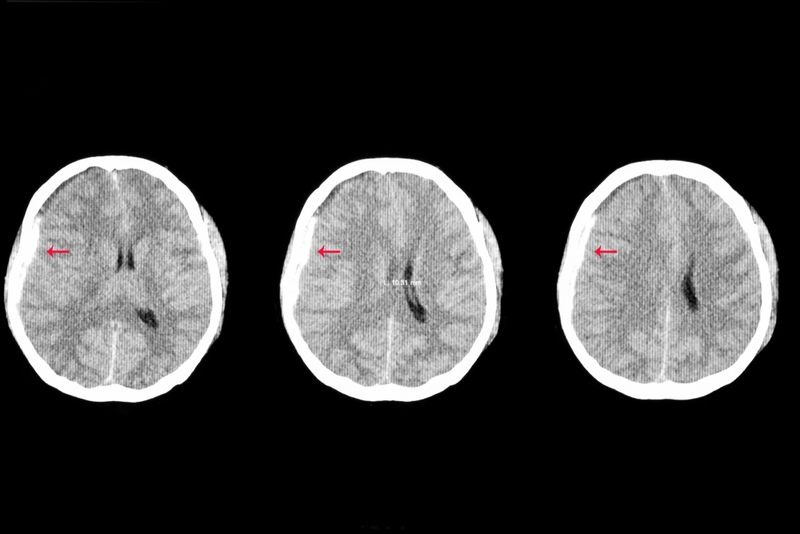

Each year in the United States, more than 600,000 children are seen in emergency rooms due to traumatic brain injury (TBI), a disruption to the normal function of the brain caused by a bump, blow, or jolt to the head. Severe TBI results in approximately 7,000 childhood deaths annually, while survivors of the condition may suffer from long-term health conditions such as seizures, learning difficulties, and communication disorders.